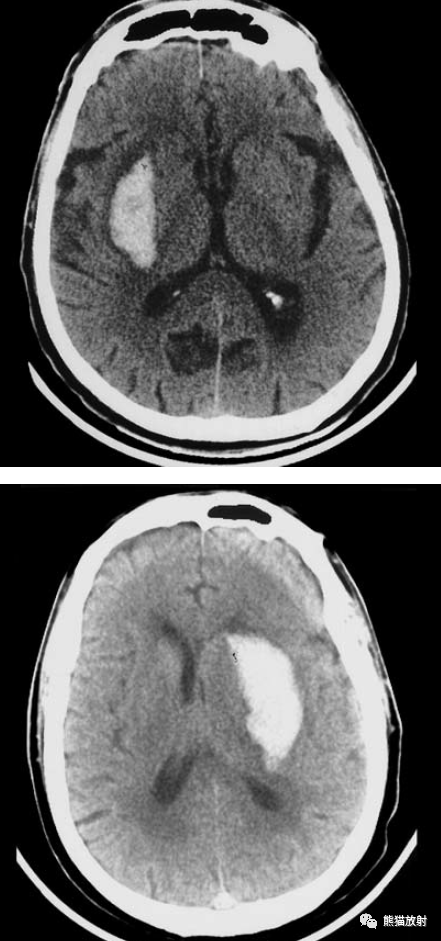

【病例讨论】外囊出血10余毫升,突发脑疝,望各位老师病情分析

检查后,诊断为脑疝,颅脑ct提示右侧外囊,基底节区脑出血并破入脑室